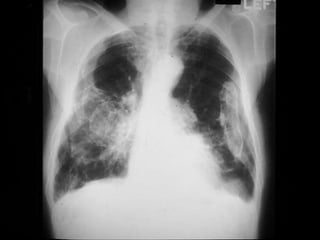

Chest X-ray of Uncomplicated

Silicosis

 Enlargement of hilar nodes may precede

parenchymal disease

 Uncomplicated silicosis has small round

opacities

 Egg-shell calcification of the hilum is

suggestive of silicosis

 Occasional can calcify

morphology

Chest X-ray ofUncomplicated Silicosis  Enlargement of hilar nodes may precede parenchymal disease  Uncomplicated silicosis has small round opacities  Egg-shell calcification of the hilum is suggestive of silicosis  Occasional can calcify